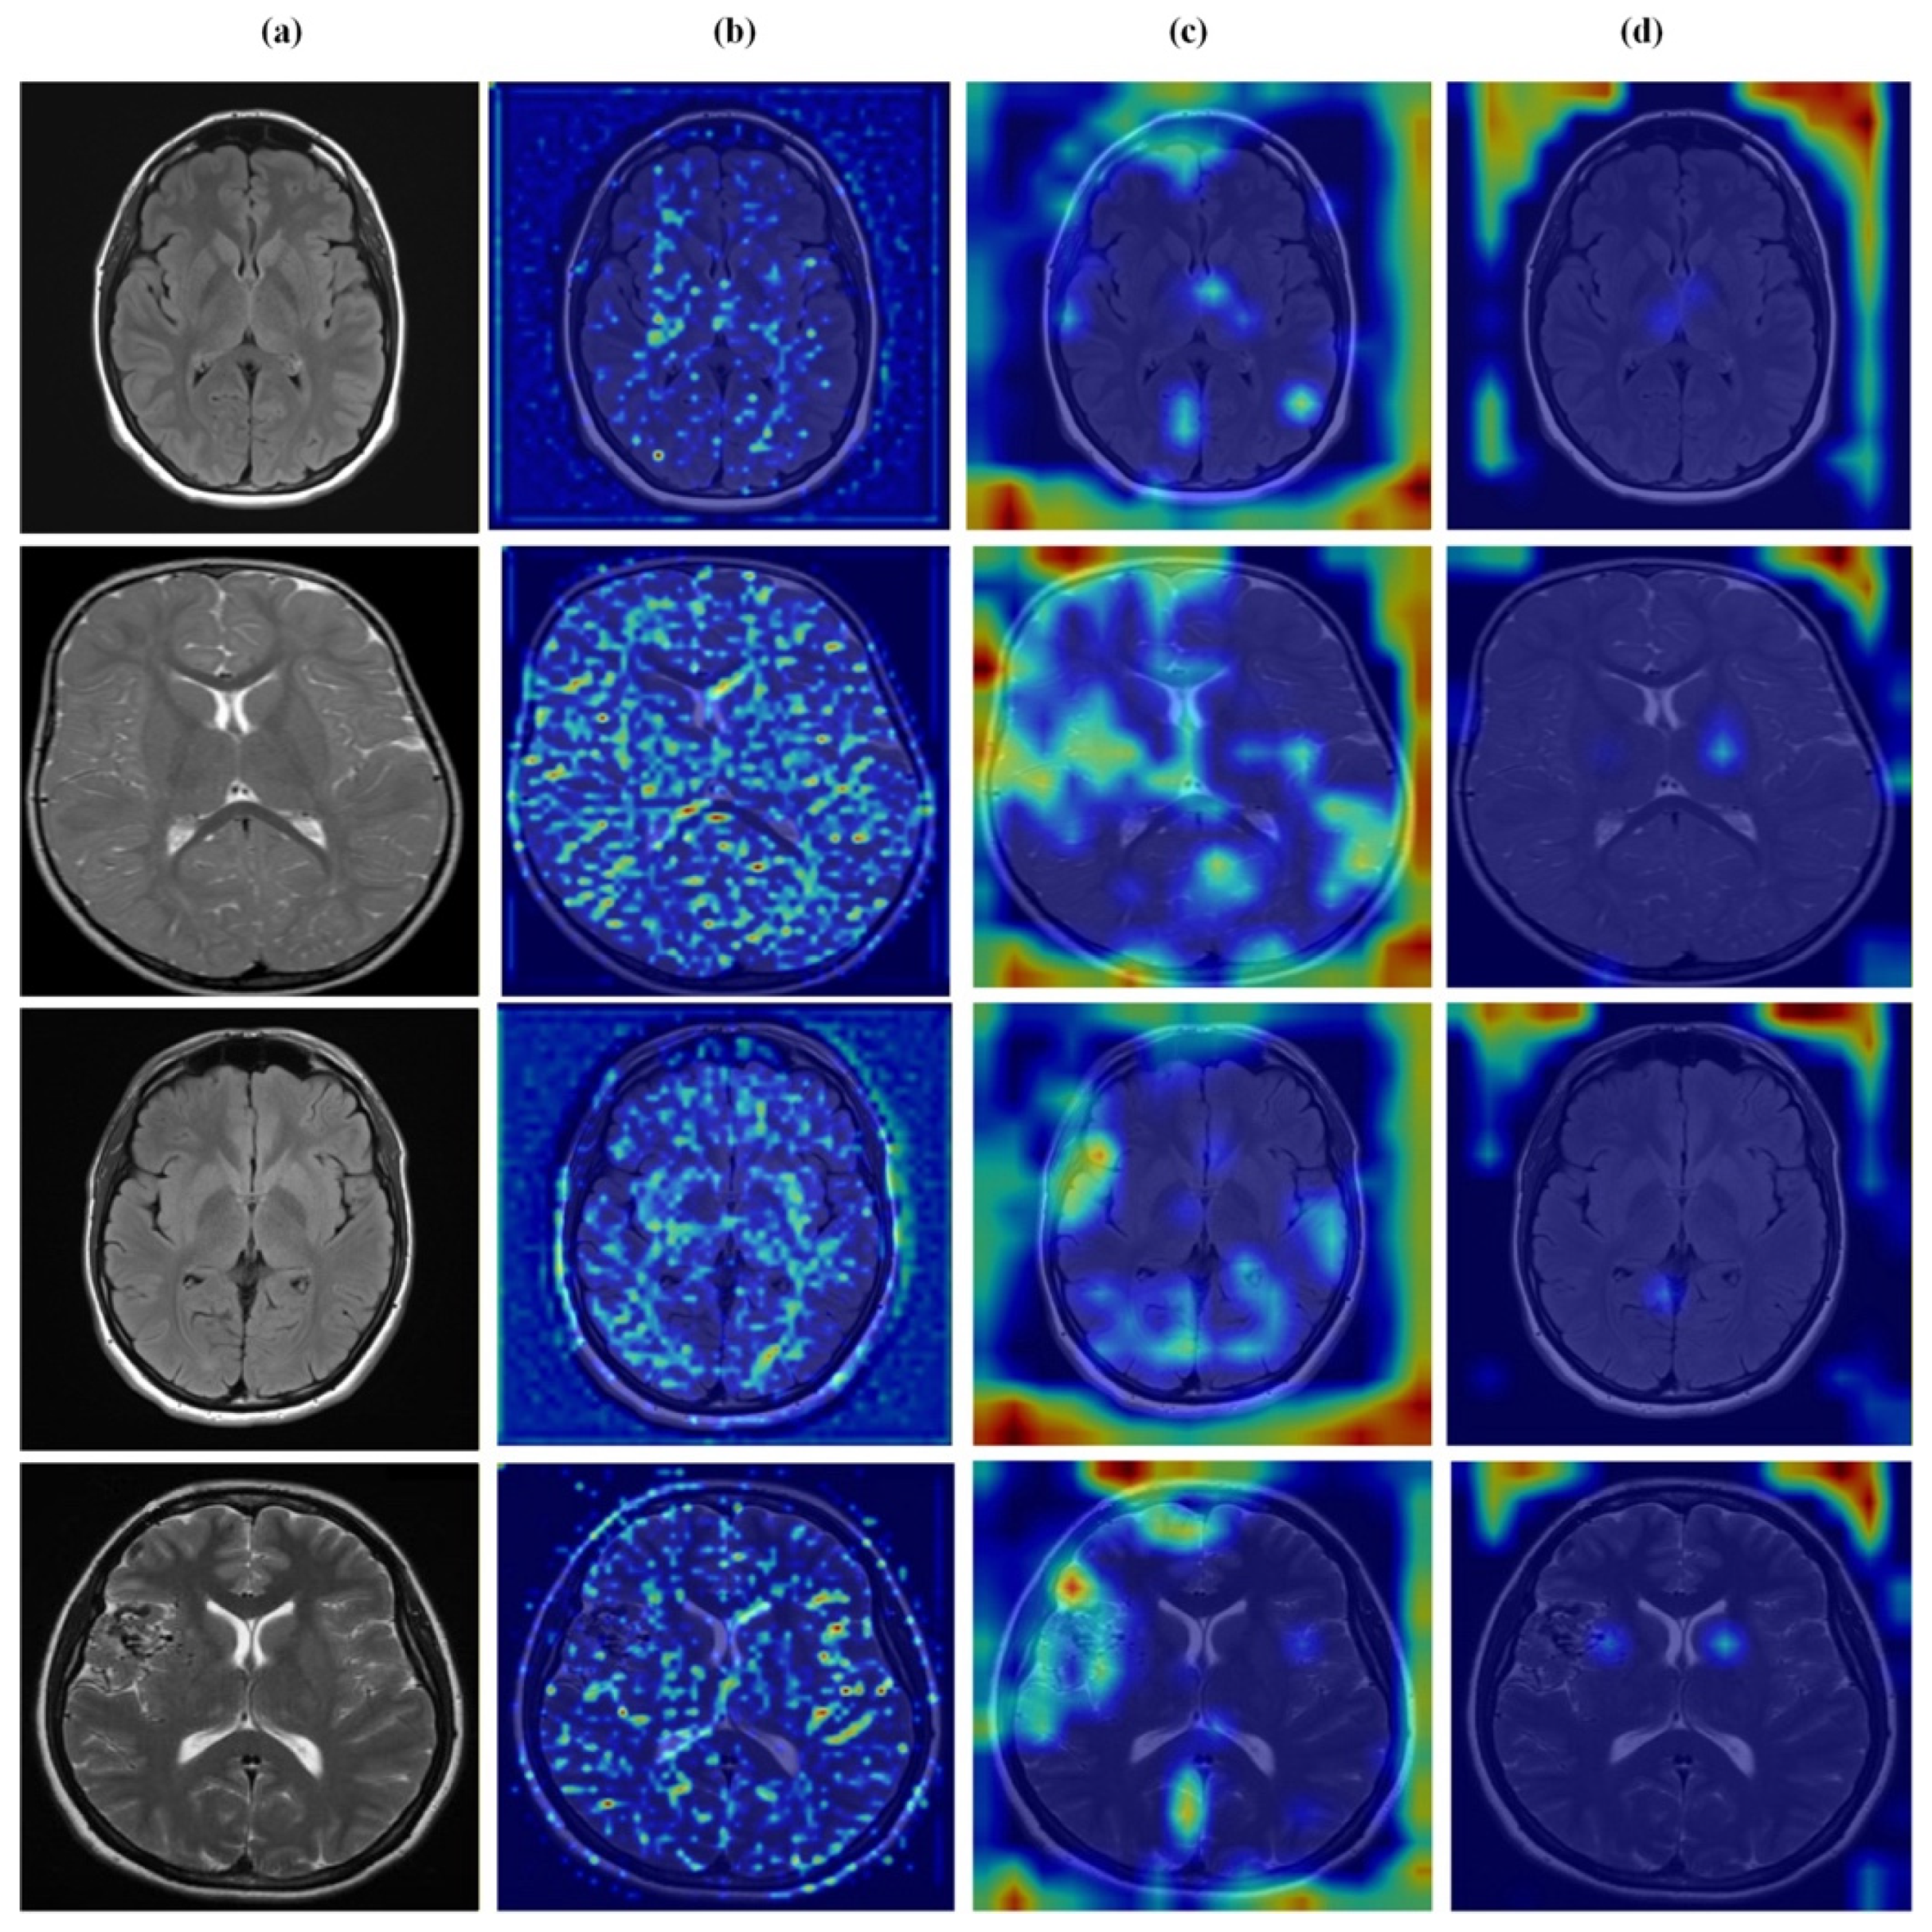

Figure 12, Figure 13, Figure 14 and Figure 15 present Grad-CAM visualizations that trace the hierarchical feature learning of the proposed model across the four classes. Columns are organized as (a) input, (b) high-level features, (c) mid-level features, and (d) low-level features. In (d), the network emphasizes primitive cue edges, intensity transitions, and fine textures capturing sulcal boundaries, skull edges, and generic tissue patterns. Progressing to (c), activations become more structured and context-aware, highlighting coherent anatomical regions and diffuse hyperintense areas that provide spatial context for lesion localization. At (b), class-discriminative focus emerges with responses that contract tumor-centric hotspots for glioma and meningioma and to the sellar region for pituitary cases, while no_tumor images exhibit suppressed high-level responses, reflecting the model’s rejection of false lesion cues. This bottom-to-top progression from generic edges to task-specific evidence explains the model’s improved decision reliability and aligns with the multi-task design that encourages precise, clinically meaningful attention.

Figure 12.

Visual representation of feature activations in no tumor cases. (a) input, (b) low-level features, (c) mid-level features, and (d) high-level features.

Figure 13.

Visual representation of feature activations in glioma tumor cases. (a) input, (b) low-level features, (c) mid-level features, and (d) high-level features.

Figure 14.

Visual representation of feature activations in meningioma tumor cases. (a) input, (b) low-level features, (c) mid-level features, and (d) high-level features.

Figure 15.

Visual representation of feature activations in pituitary tumor cases. (a) input, (b) low-level features, (c) mid-level features, and (d) high-level features.